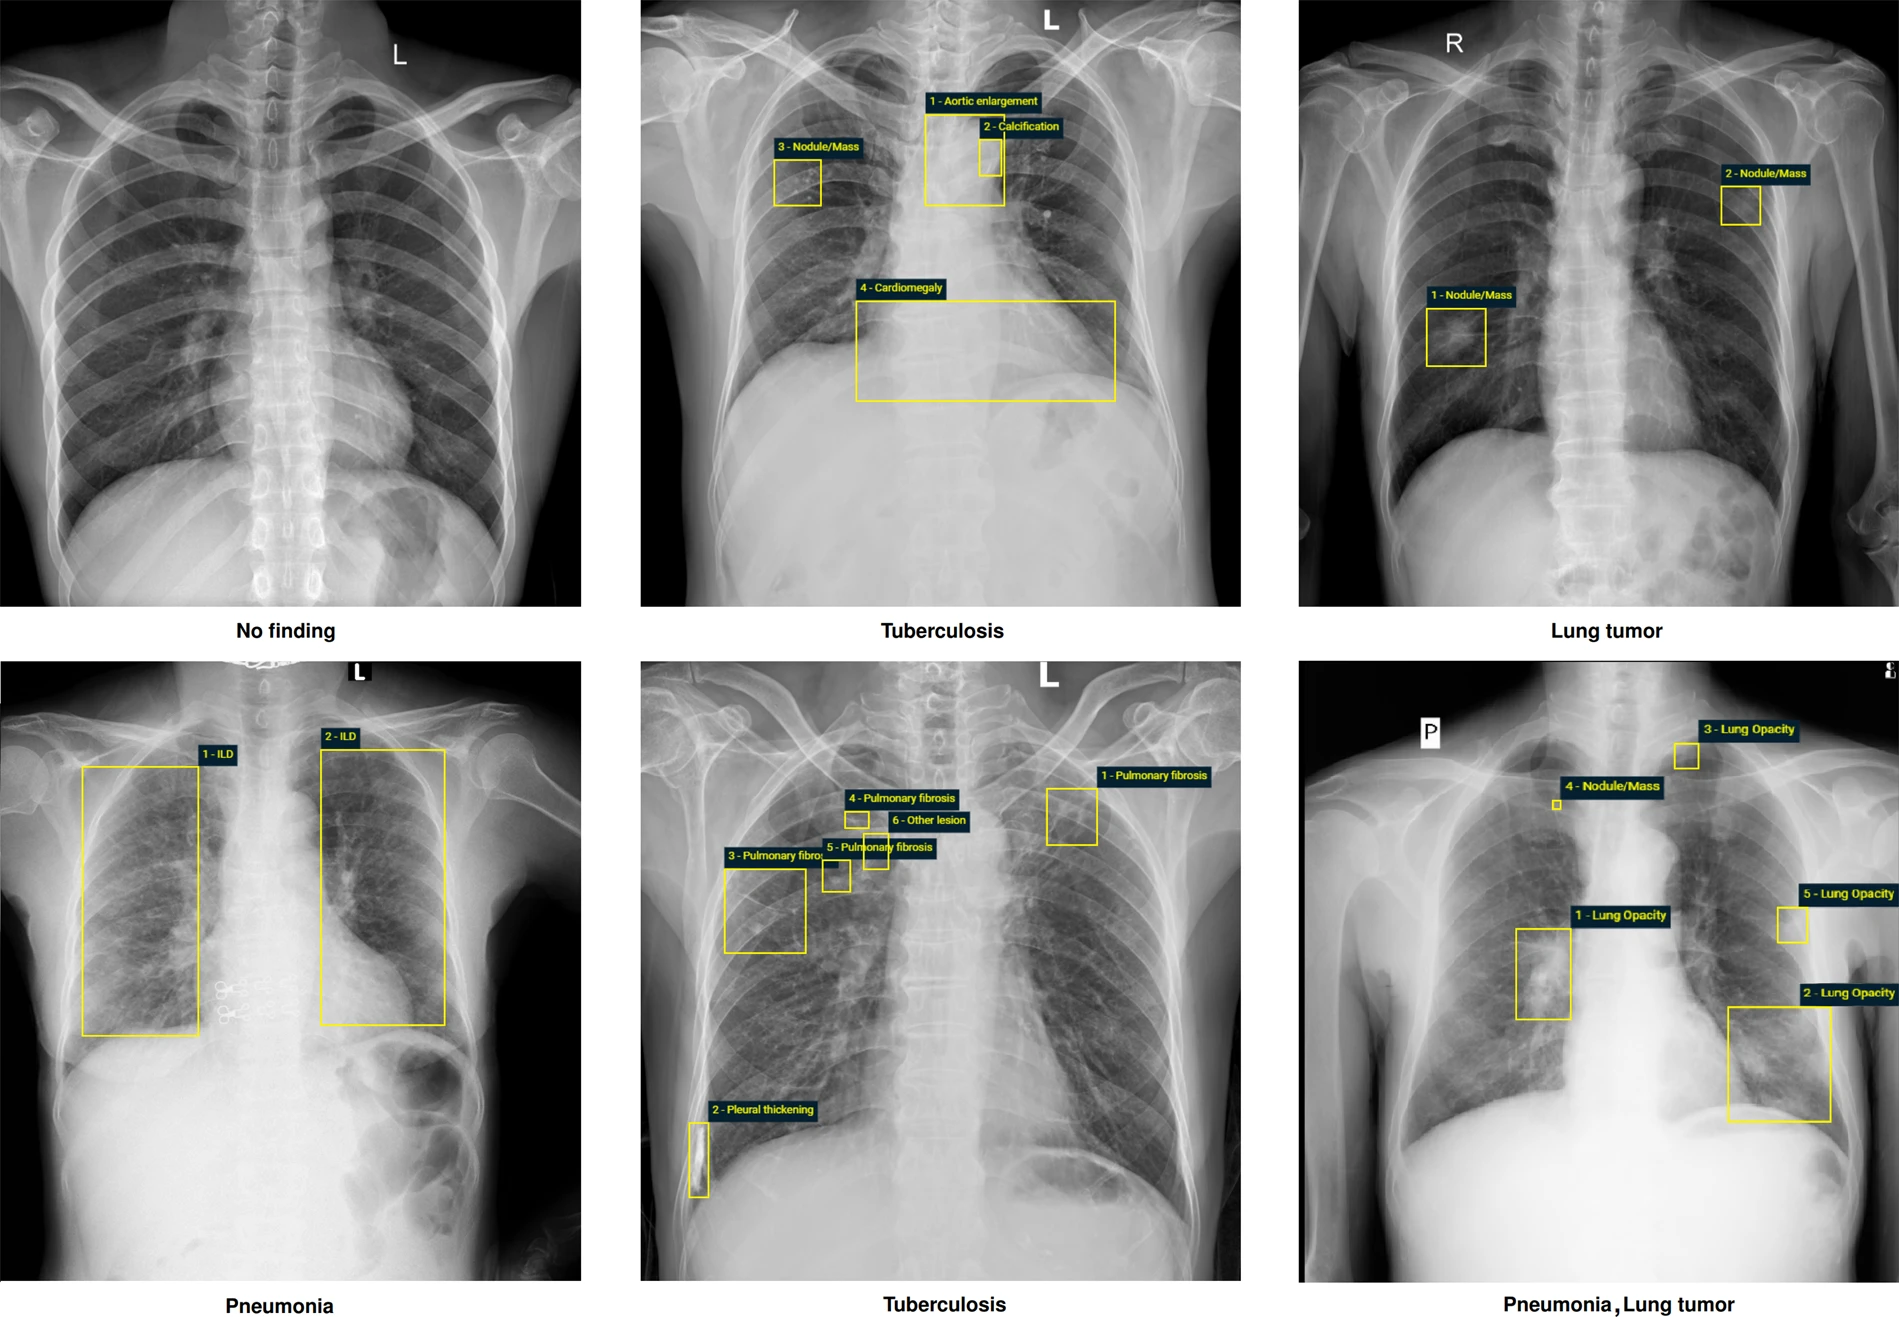

An X-Ray scan is a painless and non-invasive imaging procedure that helps healthcare providers visualize internal body structures. It uses a minimal dose of radiation to create images on a digital detector. Dense materials like bones appear white, while softer tissues display varying shades of gray.

- Chest Imaging: Identify pneumonia, lung infections, or heart abnormalities.